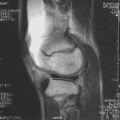

Lesão

Em esportes que impões muito impacto nos joelhos, especialmente forças de torção, é comum o rompimento de um ou mais ligamentos ou cartilagens do joelho. O ligamento cruzado anterior é frequentemente rompido como um resultado de uma rápida mudança na direção durante uma corrida ou como um resultado de algum outro tipo de movimento de torção violento. Ele também pode ser rompido com a extensão forçada além de sua amplitude normal, ou como resultado de forças sendo aplicadas lateralmente.[1]

As lesões ligamentares podem ocorrer como um resultado da força que faz com que a articulação exceda sua amplitude de movimento (ADM) normal. Uma pancada no aspecto lateral da articulação do joelho ou da tíbia pode causar um estresse em valgo que resulta no rompimento dos ligamentos impedindo movimento em valgo. Da mesma forma a hiperextensão forçada do joelho pode causar rompimento dos ligamentos posteriores. Embora forças excessivas possam causar rupturas ligamentares, força de baixa magnitude pode também causar rompimentos em ligamentos enfraquecidos pela idade, doença, imobilização, esteróides ou insuficiência vascular. Devido a esses problemas, um fortalecimento dos músculos desta complexa articulação, com a devida orientação postural, fará com que as pessoas sejam cautelosas e mais seguras na prática dos esportes tais como futebol, basquete e atletismo.

Antes do advento da artroscopia, os pacientes que faziam cirurgia para um LCA necessitavam de pelo menos nove meses de reabilitação. Com as técnicas atuais de reconstrução do LCA, estes pacientes podem hoje estar caminhando sem dificuldades em duas semanas, e praticando esportes em poucos meses.

Normalmente o tratamento de lesões no joelho podem incluir medidas como: descanso físico, órtese, fisioterapia e em alguns casos, cirurgia. As opções de tratamento são escolhidas e aplicadas dependendo da localização, tipo e gravidade da lesão, bem como a idade, condição de saúde e nível de atividade (trabalho, esporte ou hobbies).[2]